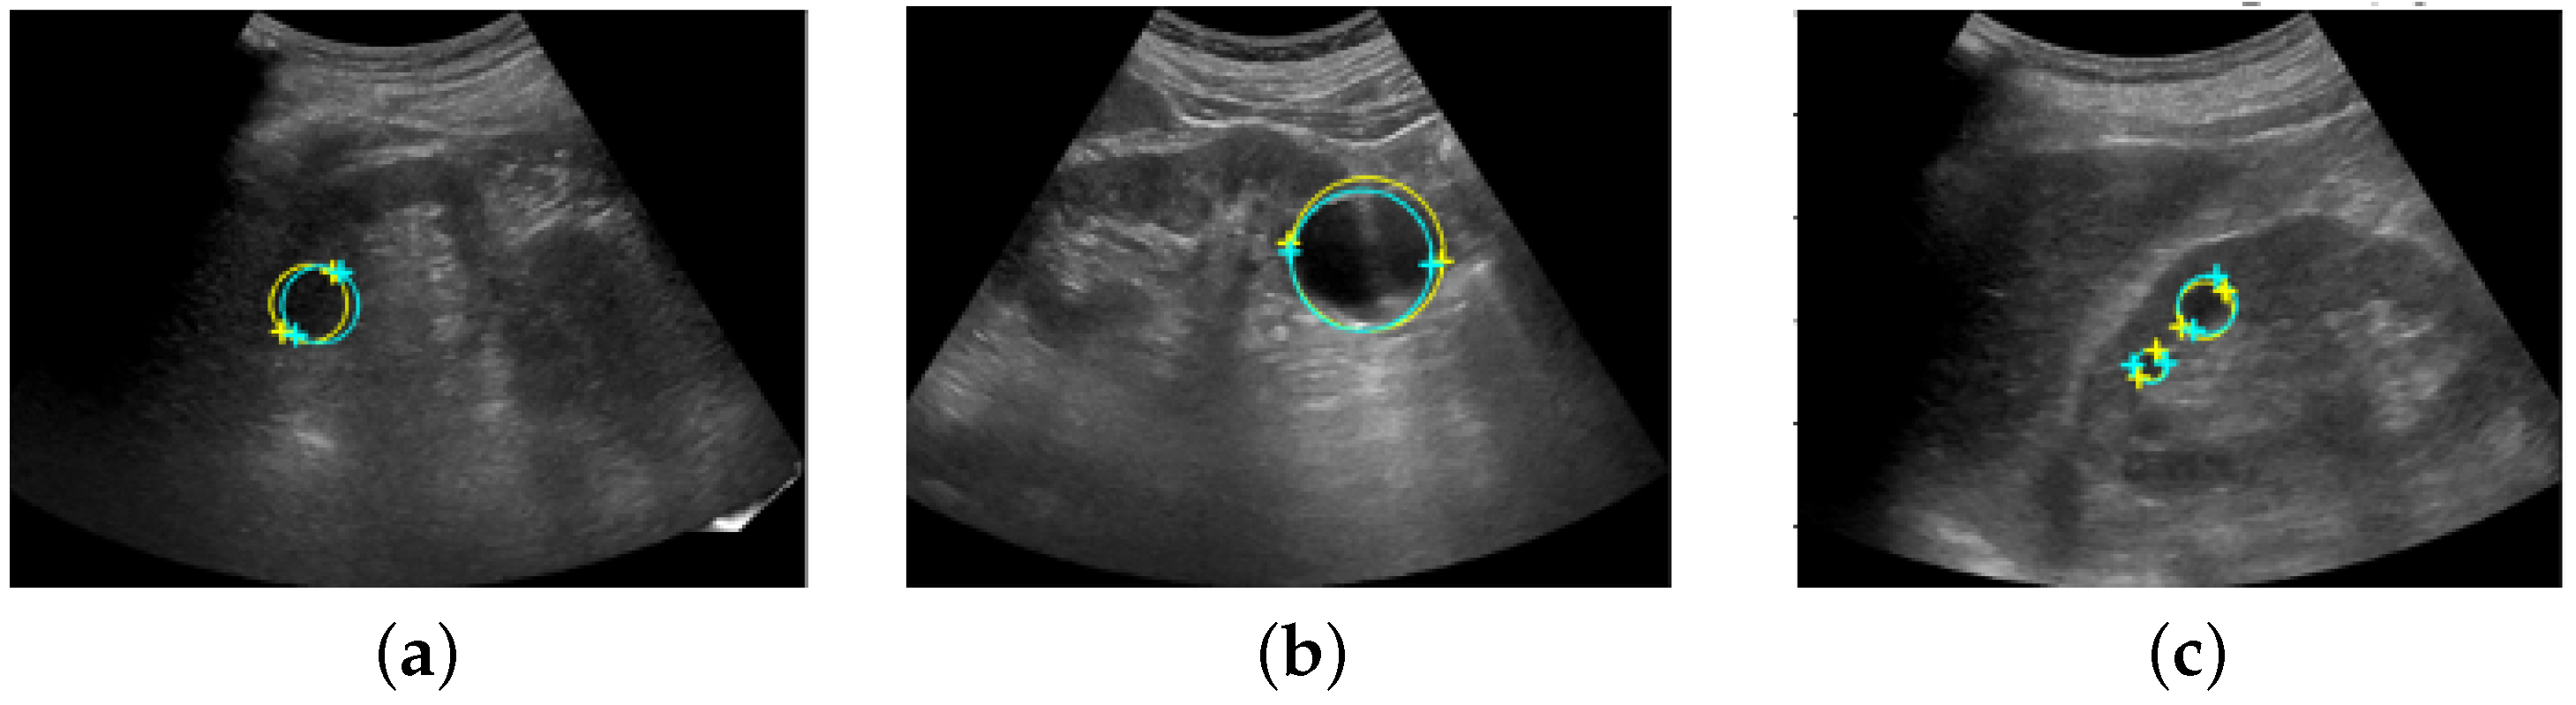

- To predict the landmarks for multiple renal cysts within one image, we developed a system in which all renal cysts in the image were detected prior to saliency map regression. Then, we performed saliency map regression to predict the positions of two salient landmarks for each detected renal cyst.

2.1. Automated System for Assigning Salient Landmarks

2.3. Saliency Map Representing the Location of Salient Landmarks

2.4. Salient Landmark Position Prediction Model